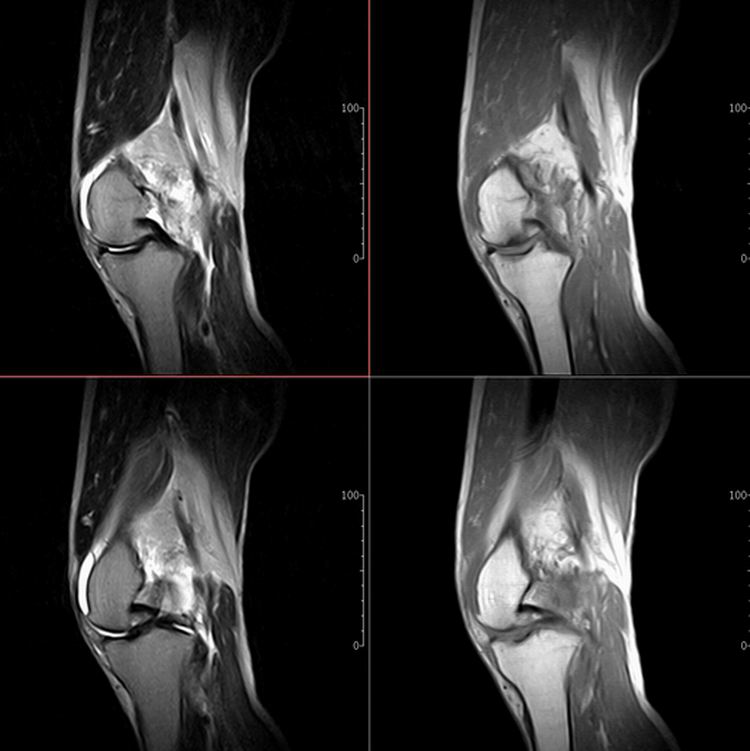

标题: MRI1910:M 687Y。近日因外伤疼痛,而就诊。

m 687y。近日因外伤疼痛,而就诊。有外侧副韧带损伤吗??因片子较差各位请包涵。

有韧带损伤

关节退行性变伴股骨外髁关节面下囊肿,不除外剥脱性骨软骨炎.关节积液,髌骨软化症

体位不标准。关节退变伴关节积液。

1)膝关节骨质退行性改变。

2)由于体位的关系不能确定有外侧副韧带的损伤。

关节退变伴关节积液,外侧副韧带的损伤

关节积液,外侧副韧带的损伤